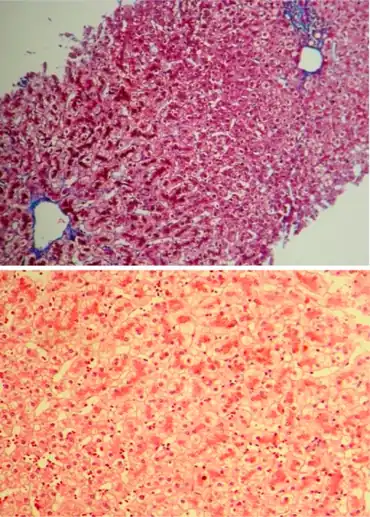

It is inherited as autosomal recessive, and causes an isolated increase of conjugated bilirubin in the serum.[5] The liver typically appears black due to the deposition of a pigment similar to melanin.[5] This condition is associated with a defect in the ability of hepatocytes to secrete conjugated bilirubin into the bile, and is similar to Rotor syndrome.[5] It is usually asymptomatic, but may be diagnosed in early infancy based on laboratory tests.[5] No treatment is usually needed.[5]

Impaired biliary excretion of bilirubin glucuronides is due to a mutation in the canalicular multiple drug-resistance protein 2 (MRP2). A darkly pigmented liver is due to polymerized epinephrine metabolites, not bilirubin.[9]

In post mortem autopsy, the liver will have a dark pink or black appearance due to pigment accumulation.

| Appearance of liver | normal histology and appearance | liver has black pigmentation |